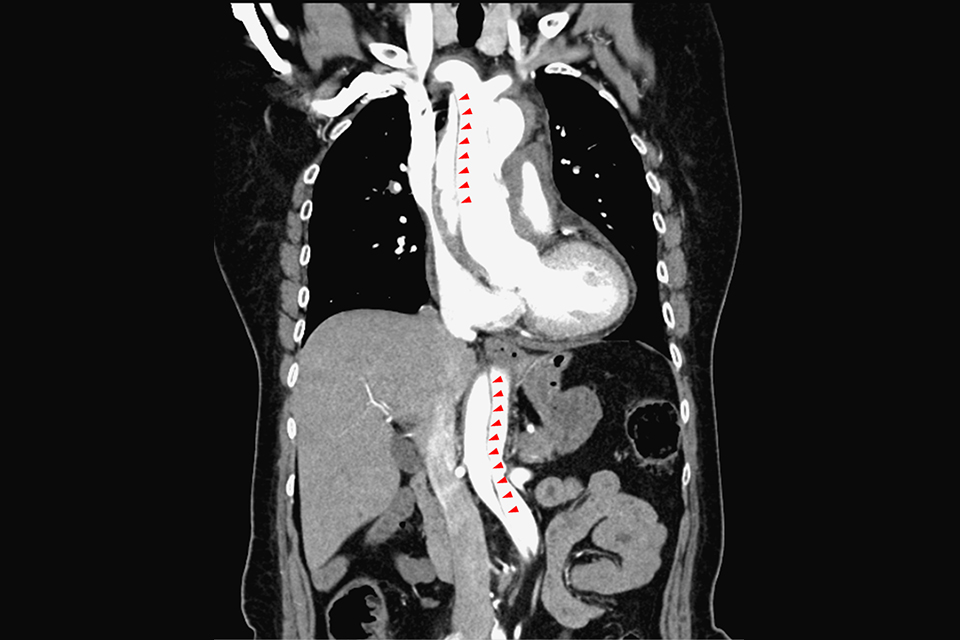

進一步分析,主動脈(Aorta)是身體最大動脈,由3層結構內膜(intima)、中膜(Media)、外膜(Adventitia)所組成。李穎灝說明,當心臟打出血液後,透過主動脈將血液輸送全身各處,一旦血管壁經長年血流沖刷及慢性病摧殘後,內層可能形成裂縫,血液流入內層與中層之間,形成「假腔」,擠壓到「真腔」(正常的血流途徑),進而導致血液供應受阻。

主動脈剝離依發病位置,分為A、B兩型。狀如拐杖的主動脈,上行部分稱為升主動脈,轉彎部分是主動脈弓,下行部分則為降主動脈。剝離位置影響到升主動脈的屬於A型,未影響升主動脈的則為B型。A型容易產心臟相關的併發症,死亡率較B型高,若未緊急手術,發病48小時內致死率可高達50%。